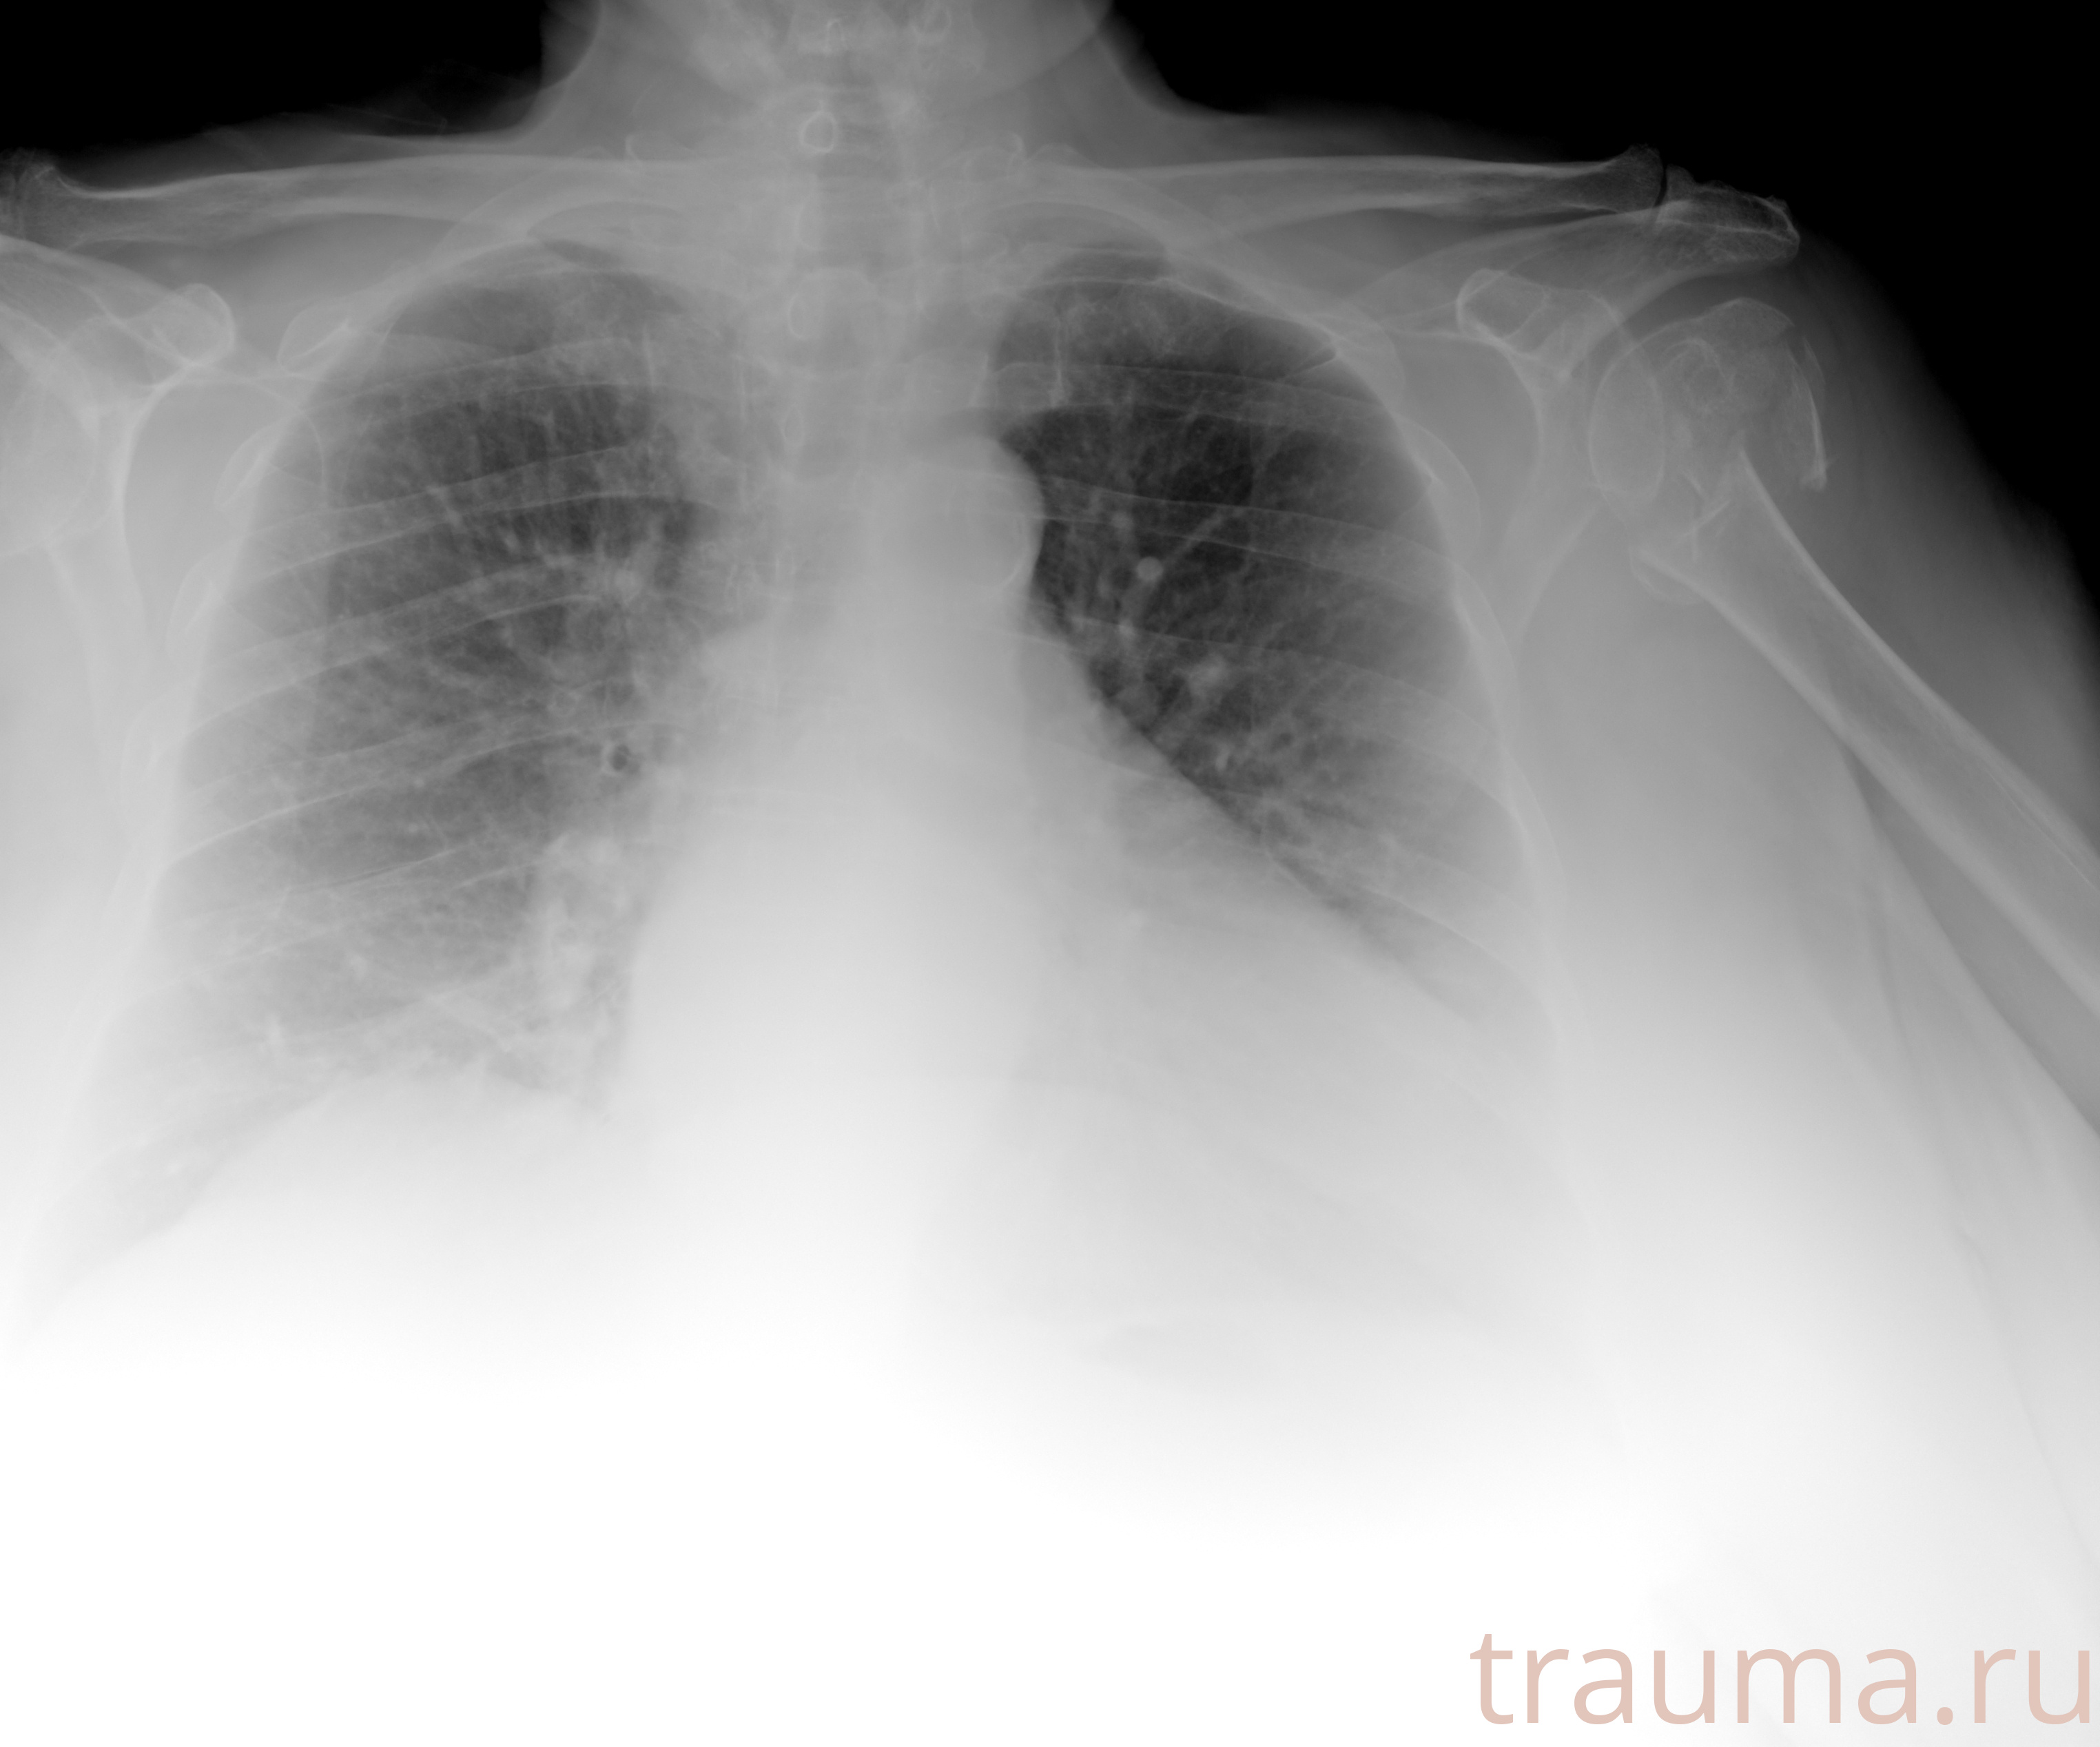

Рентгенограммы

Рентген на дому: по вашему адресу приезжает врач-рентгенолог, травматолог-ортопед с мобильным рентгеновским аппаратом, проводит диагностику травмы или заболевания, делает необходимые рентгенограммы, дает рекомендации по дальнейшему лечению. Получить качественные снимки в домашних условиях возможно благодаря уникальной методике, разработанной МосРентген Центром для института  Склифосовского

при переломе шейки бедра и пневмонии от компании МосРентген Центр - партнера Института имени Склифосовского